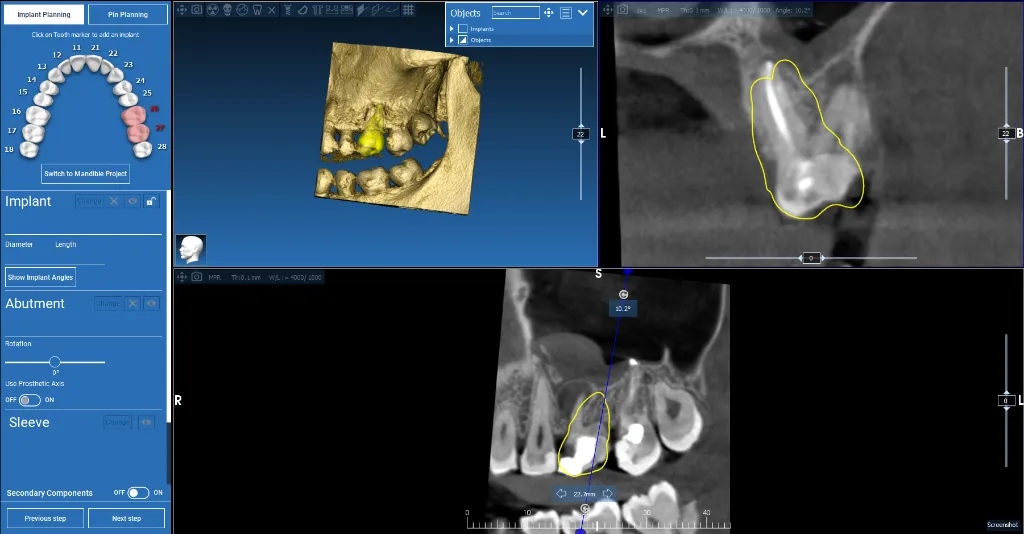

Maxillary Implant Case — 3 Implants

Tooth-supported guide for 3 implants in the upper jaw. Digital planning with precise implant positioning.